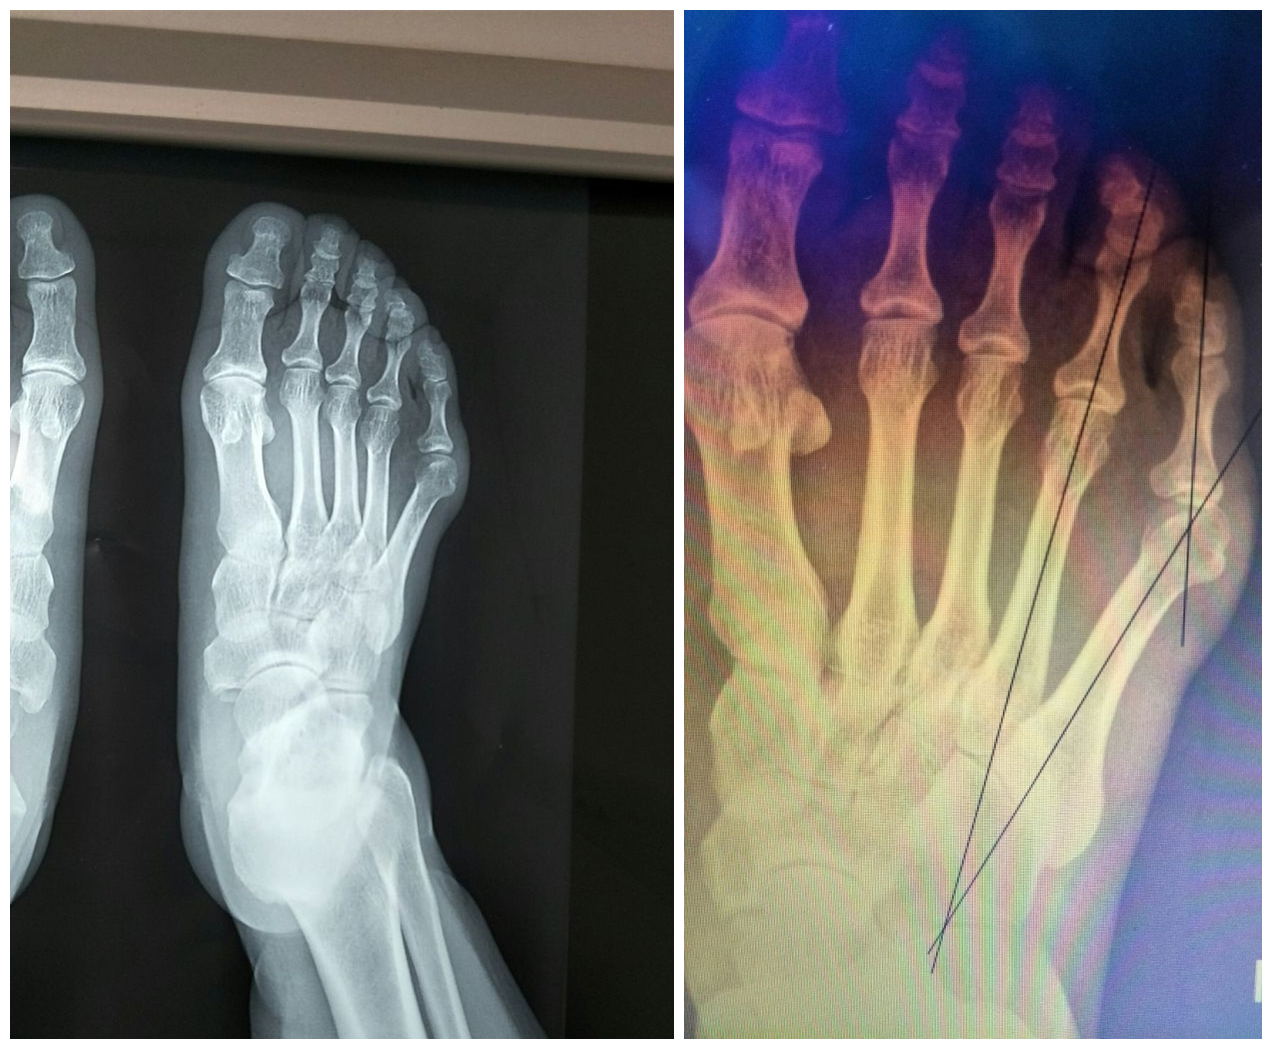

右足正侧位X光片:右足第5跖骨头外侧骨赘形成,第4.5跖骨间角增大(20°),小趾跖趾关节角增大(20°)。诊断:小趾囊炎(III型,右)。

右足正侧位X光片:右足第5跖骨头外侧骨赘形成,第4.5跖骨间角增大(20°),小趾跖趾关节角增大(20°)。

术后拍片复查:右足第4.5跖骨间角恢复正常(4.5跖骨间角7°),小趾跖趾关节角恢复正常,第5跖骨头高度良好。